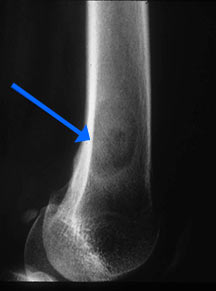

- May arise from any bone and any site within a bone (epiphyseal, metaphyseal, diaphyseal)

- Radiographically variable appearance: may appear benign (geographic) or malignant (permeative or moth eaten)